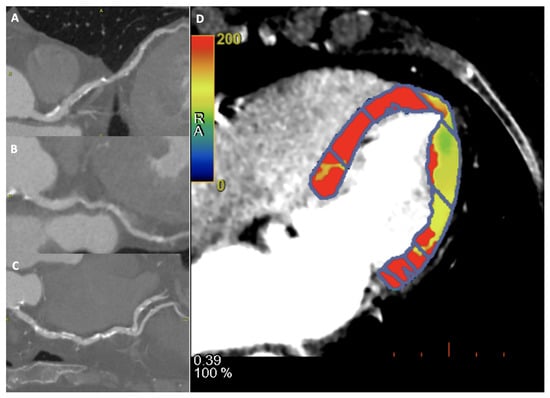

Figure 3.

A 60-year-old female patient underwent to CCTA and dynamic CT perfusion for suspected coronary artery disease. Diffuse coronary calcification on left anterior descending artery (A), left circumflex (B) and right coronary (C), showing mild reduction of flow in dynamic CT perfusion on lateral wall, in particular at the apical segment (D).